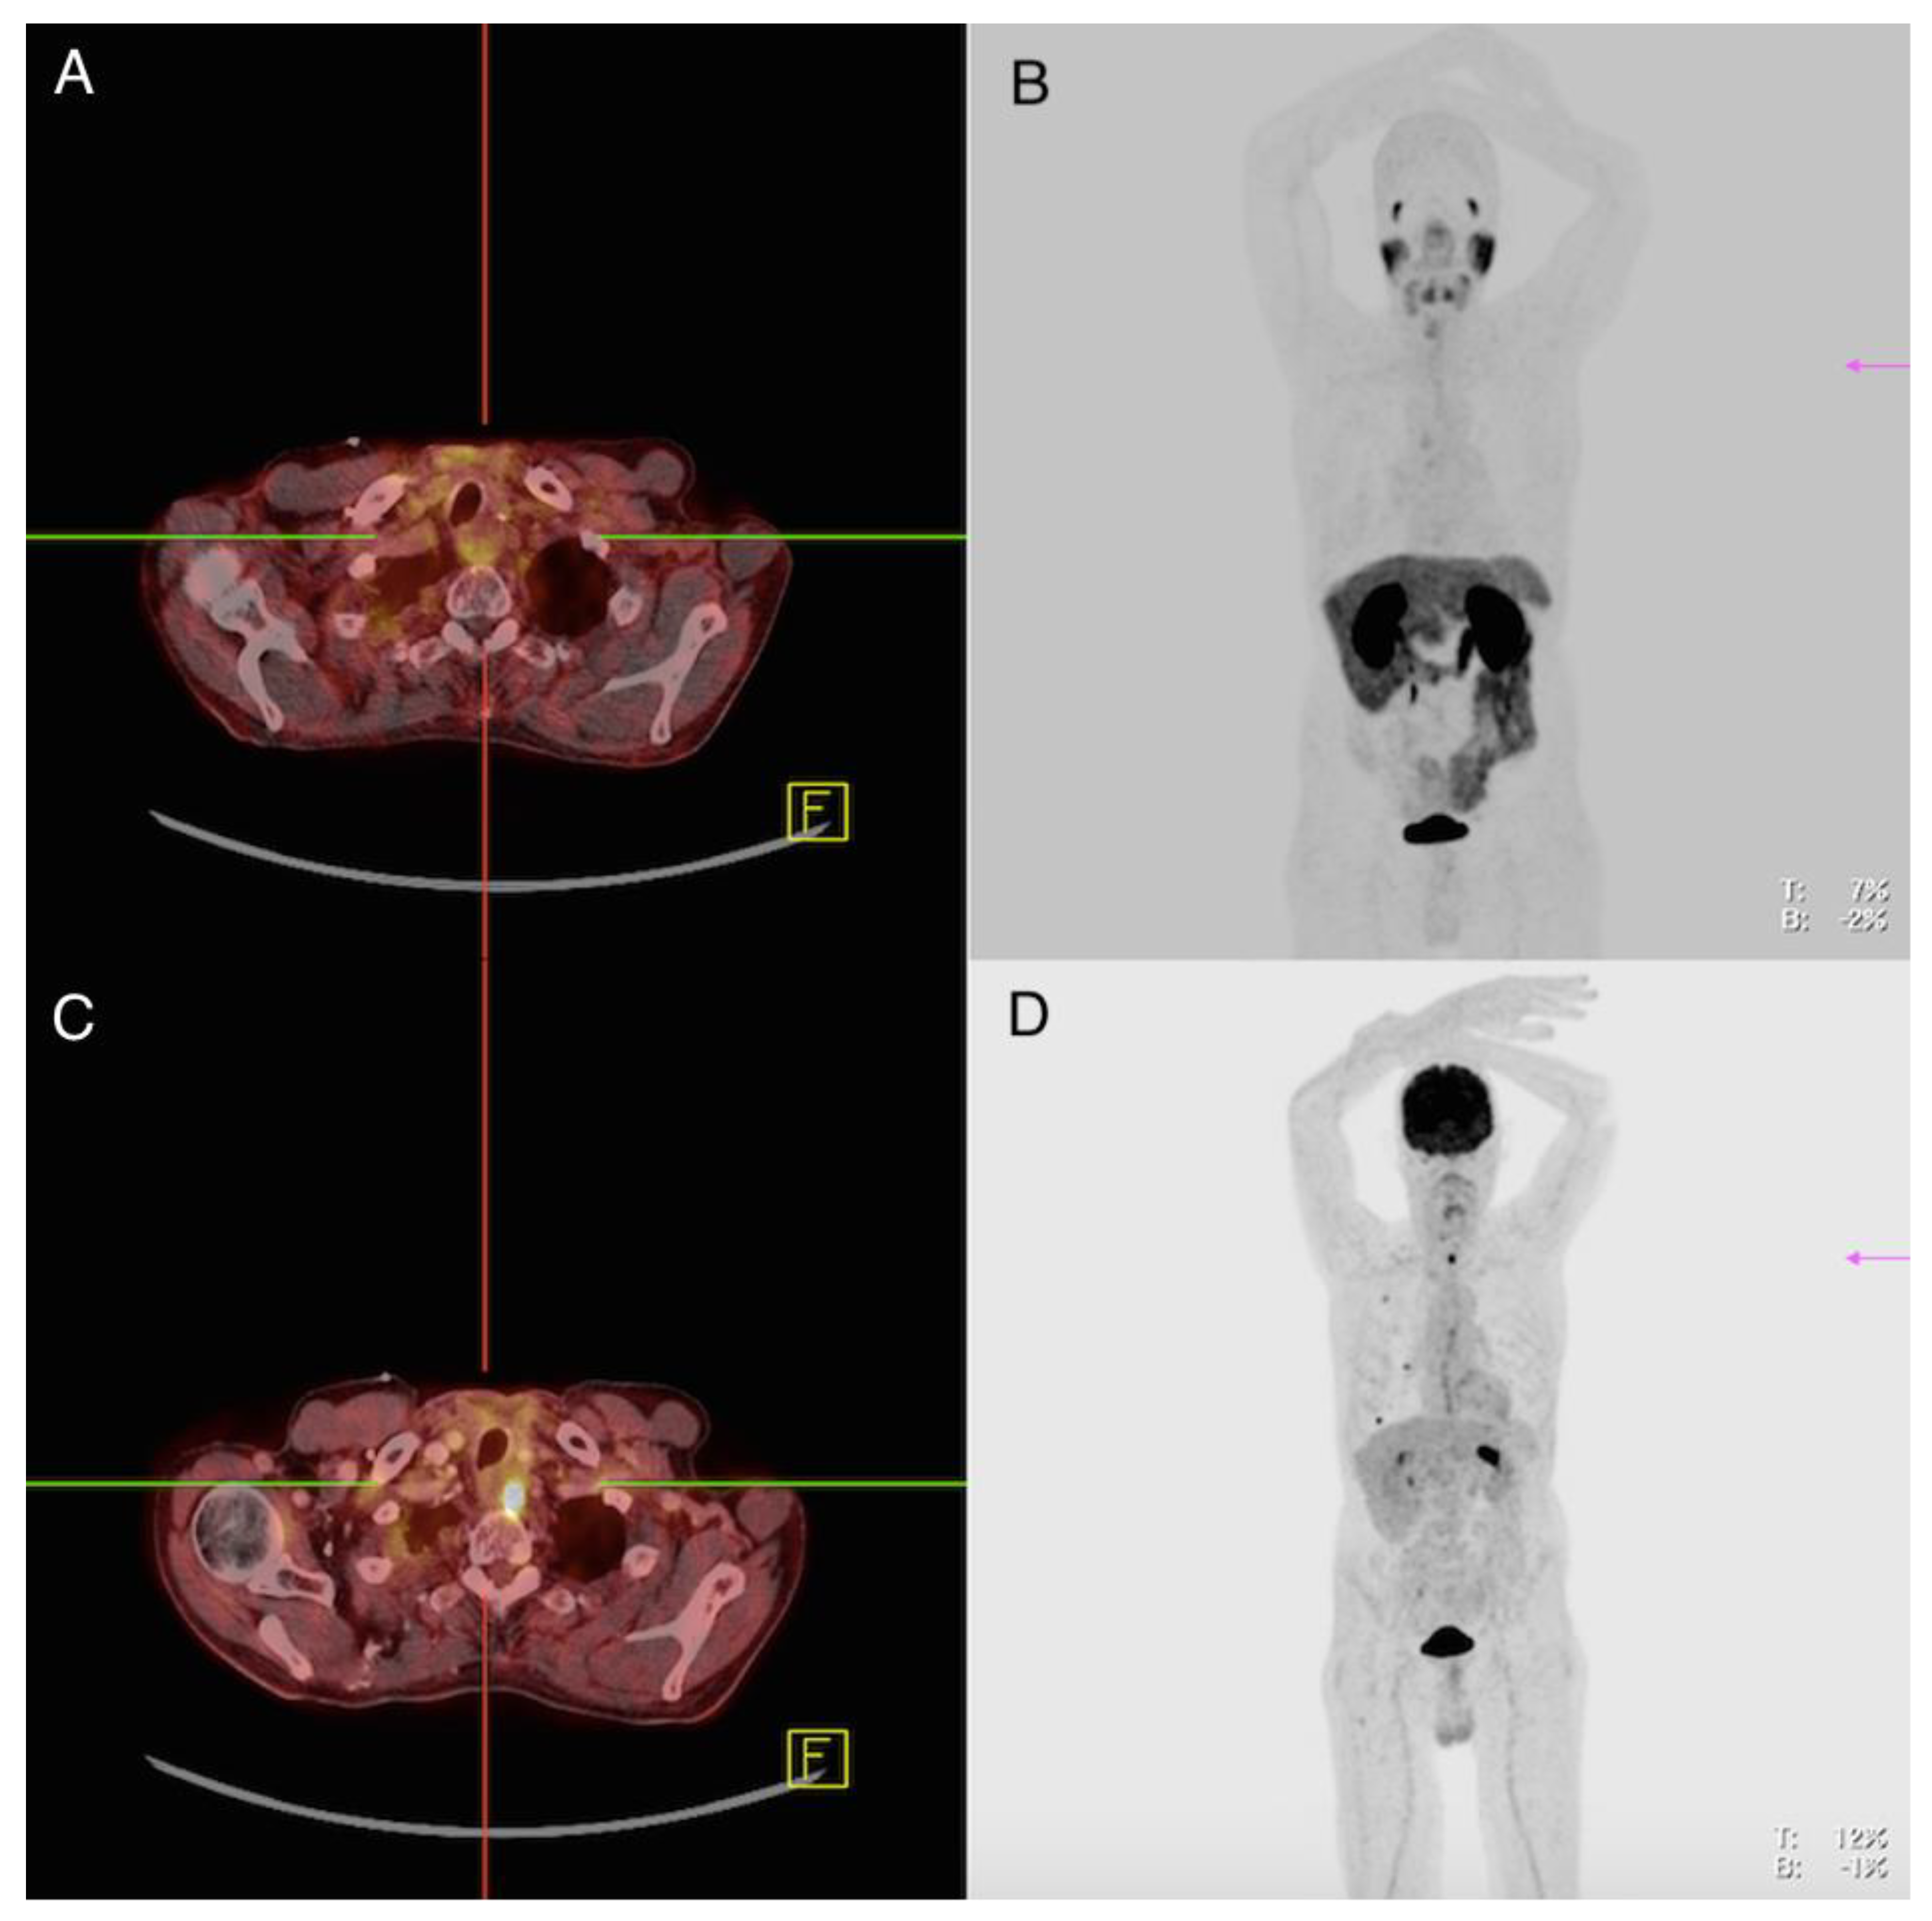

Patient 1: Male, ATC, 59 Years Old at the Time of Diagnosis

Patient 7: Female, PDTC, 61 Years Old at the Time of Diagnosis

Patient 8: Male, PDTC, 59 Years Old at Time of Diagnosis

| 1 | M | 59 | 2020 | ATC | pT4a pN0 M0 | IVB | Surgery of the thyroid gland (2020) Radiochemotherapy (2020) Targeted therapy (Pembrolizumab + Lenvatinib) (2020/2021) |

| 7 | F | 61 | 2013 | PDTC | pT3a pN1 M1 | IVB | Surgery of the thyroid gland (2013) Twofold radioiodine therapy (cumulative 9,9 GBq I-131) (2013) Surgery of cervical lymph node metastasis (2014) Lutetium-177-DOTATATE therapy (2014) mKI therapy (Sorafenib) (2014) External beam therapy of vertebral and cervical lymph node metastases (2016) mKI therapy (Lenvatinib) (2016) Surgery of brain metastases (2018) |

| 8 | M | 59 | 2015 | PDTC | pT0 cN0 M1 | IVB | Surgery of the thyroid gland (2011) Surgery of vertebral metastasis (2015) Residual thyroidectomy without tumor detection (2015) Radioiodine therapy (14,9 GBq I-131) (2015) Two cycles of Lutetium-177-PSMA therapy (cumulativ 13,7 GBq) (2017) mKI therapy (Lenvatinib) (2018) COSMIC study 2 inclusion (2020) |

| 1 | 2020 | PSMA: 2020 FDG: 2020 | 1 | TB 1 (local recurrence) (n = 1) 1.9 | 16.3 | 2.5 | Primary tumor Soft tissue surrounding thyroid gland | Strong expression Strong expression |

| LN2 (mediastinal) (n = 1) 2.2 | 2.7 | 3.3 | ||||||

| PM 3 (n = 7) 0.7 (0.3–1.2) | 2.7 (1.5–7.9) | 1.3 (0.6–2.6) | ||||||

| 2 | 2020 | PSMA: 2020 FDG: 2020 | 1 | PM 3 (n = 2) 2.1; 2.2 | 21.2 (14.1; 28.3) | 3.25 (4.0; 2.5) | Primary tumor Pulmonary metastasis | Strong expression Strong expression |

| 7 | 2013 | PSMA: 2017 FDG: 2016 | 76 | CM 5 (n = 1) 2.9 | 31.4 | 12.3 | Primary tumor Lymph node metastasis (cervical) | Strong expression Strong expression |

| LN 2 cervical (n = 1) 2.0 mediastinal (n = 2) (3.6; 1.4) inguinal (n = 1) 5.4 | 32.1 30.85 (36.4; 25.3) 35.2 | 7.4 8.2 (6.3; 10.1) 6.2 | ||||||

| PM 3 (n > 10) 1.1 (1.0–1.8) | 12.5 (11.7–14.1) | 3.3 (2.1–4.0) | ||||||

| ST 6 (thoracic wall) (n = 1) 2.1 | 31.0 | 4.3 | ||||||

| OM 4 (Os occipital) (n = 1) 2.9 | 16.9 | 7.2 | ||||||

| 8 | 2015 | PSMA: 2016 FDG: 2016 | 81 | OM 4 (n = 4) 1.25 (0 *–1.6) | 2.3 (1.2–2.7) | 5.55 (2.9–9.0) | No tissue sample of this patient was available | |